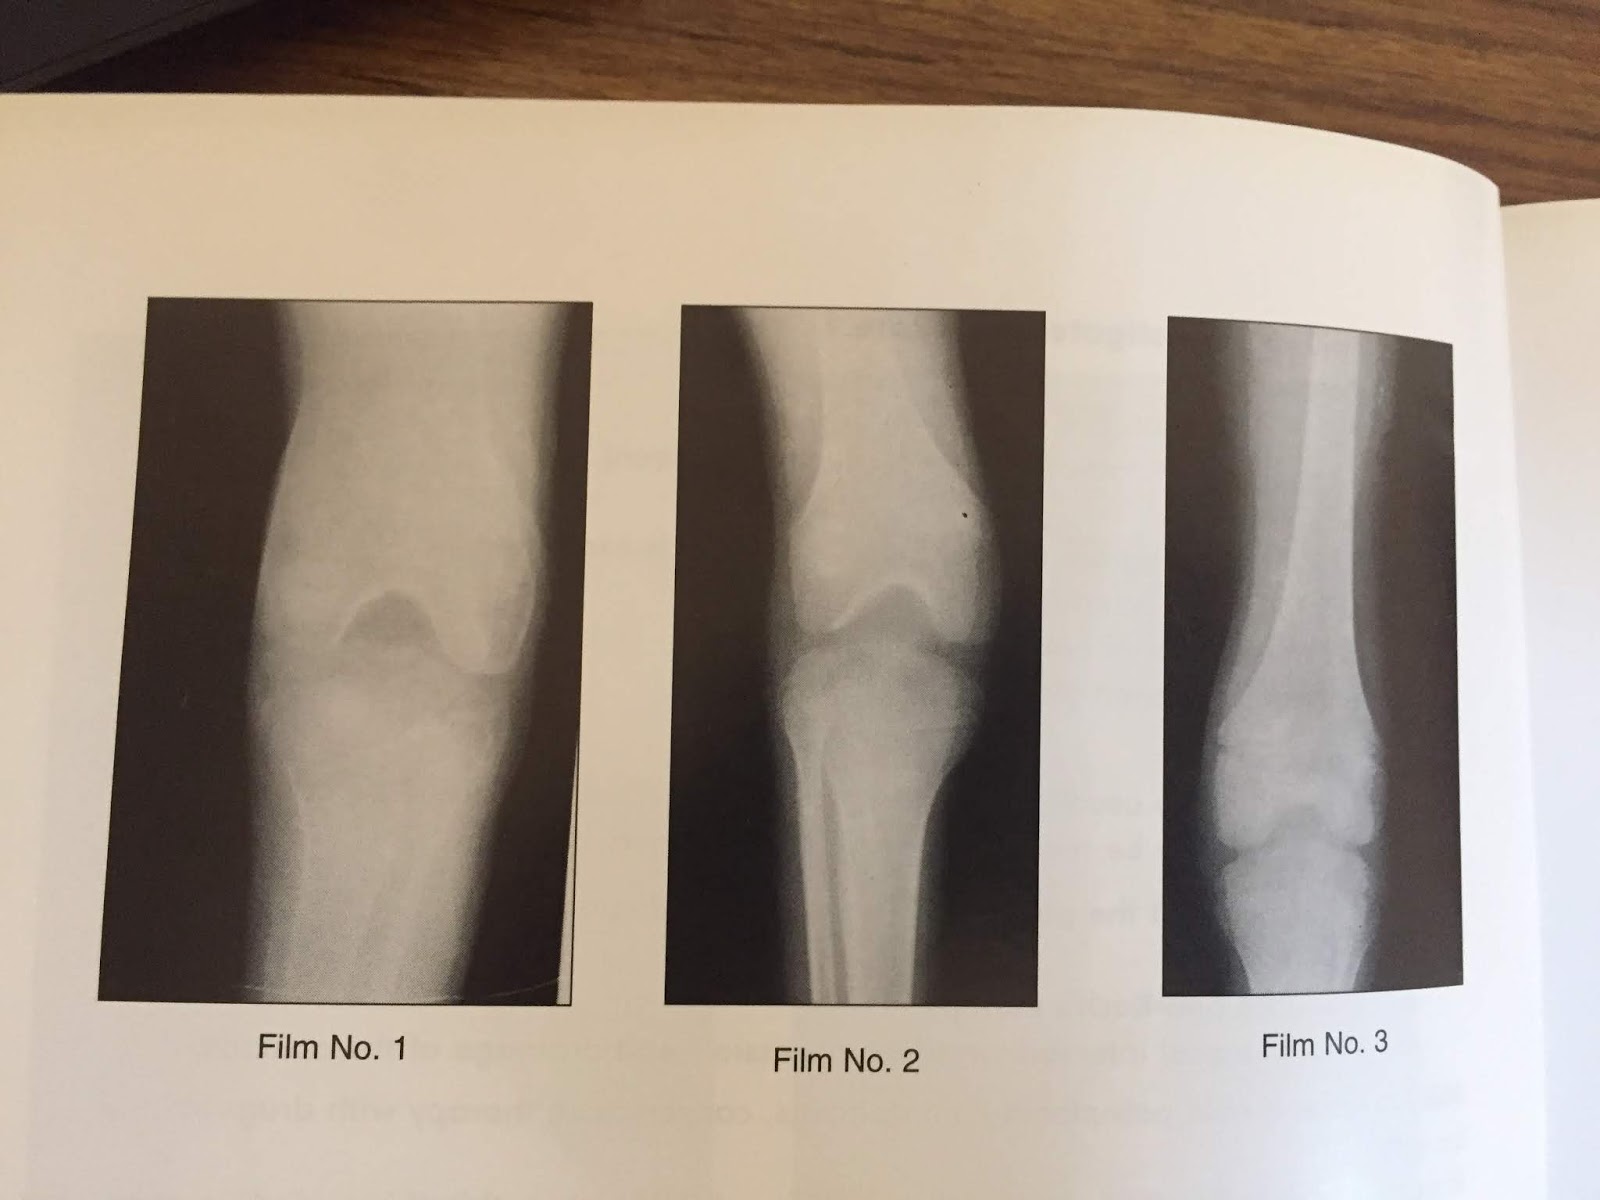

XRAYS OF HEMOPHILIC ARTHRITIS Hemophilic Arthritis Def hemophilic arthropathy, a crippling condition that has a serious effect on functionality and quality of life, is caused by frequent hemarthrosis. hemophilia a and b are rare, inherited x‐linked bleeding disorders. hemophilic arthropathy is a disabling condition characterized by joint. hemophilic arthropathy is a form of joint disease that develops secondary to joint bleeding and presents. Hemophilic Arthritis Def.

XRAYS OF HEMOPHILIC ARTHRITIS Hemophilic Arthritis Def hemophilic arthropathy is a form of joint disease that develops secondary to joint bleeding and presents with synovial. hemophilic arthropathy is a disabling condition characterized by joint. recurrent joint bleeding causes synovial proliferation and inflammation. hemophilic arthropathy, a crippling condition that has a serious effect on functionality and quality of life, is caused by frequent hemarthrosis.. Hemophilic Arthritis Def.